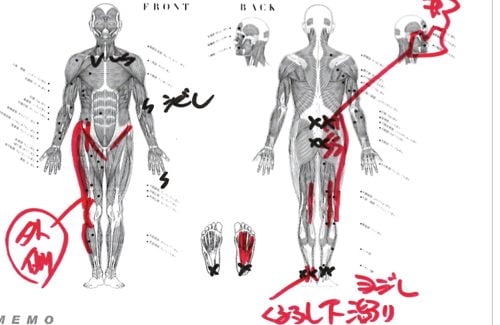

実際にお身体の状態を触診して確認してみるとこんな感じでした。

赤い線は筋肉や腱の硬直やヨジレ

Xは痛み ✔は痺れの場所

以前にヘルニアの手術後に歩けなくなってしまった女性の状態と似ていて膝から足の先、そして膝から鼠径部に向けて筋肉や腱・靭帯の硬直やヨジレがありました。

特にクルブシ付近と足裏のヨジレが大きくそこが足の指に力が入らない原因でした。

これらの硬直やヨジレはレントゲンやMRIには写りません。